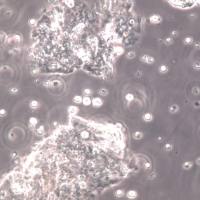

- 细胞形态:

悬浮

- 生长状态: